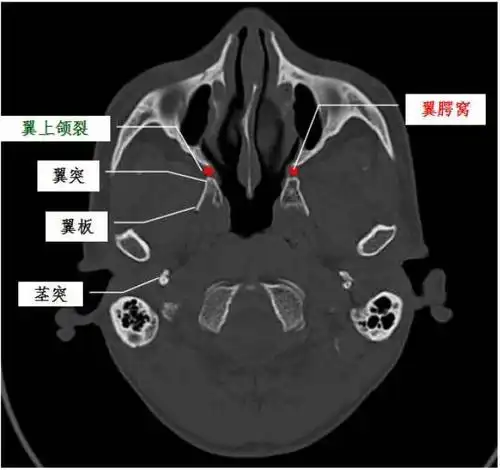

下:翼腭管---腭大,小孔---口腔外:翼上颌裂---颞下窝内:蝶腭孔---鼻腔